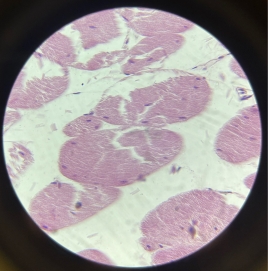

Cardiac Muscle

Cardiac Muscle

Cardiac Muscle

Cardiac Muscle

Cardiac Muscle